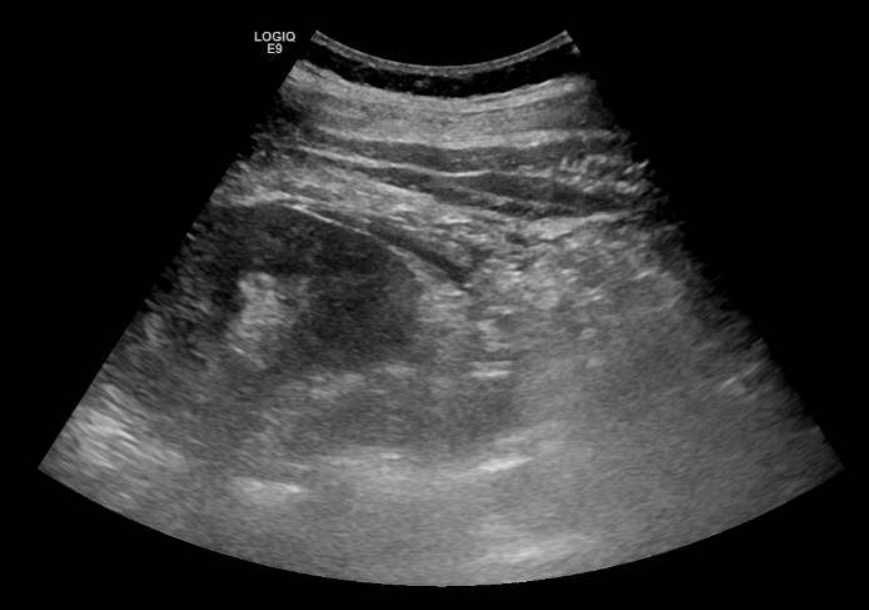

Se solicita ecografía abdominal que muestra líquido en espacio pararrenal posterior derecho bajo, sobre músculo psoasilíaco derecho, y leve ectasia piélica derecha sin identificar causa.

Entre las entidades que afectan al espacio pararrenal nos encontramos linfangioma, entidades fibróticas, hematomas, abscesos, neoplasias… Por tanto, se completa estudio con TAC abdominal con contraste. En el TAC se observa litiasis de 3 mm en meato ureteral derecho con dilatación pielocalicial grado II y leve-moderada cantidad de líquido en espacios retroperitoneales peri y pararrenal derechos, que se relacionan con salida de contraste intravenoso en fase excretora, compatible con rotura de la vía urinaria sin identificarse claro punto de fuga.